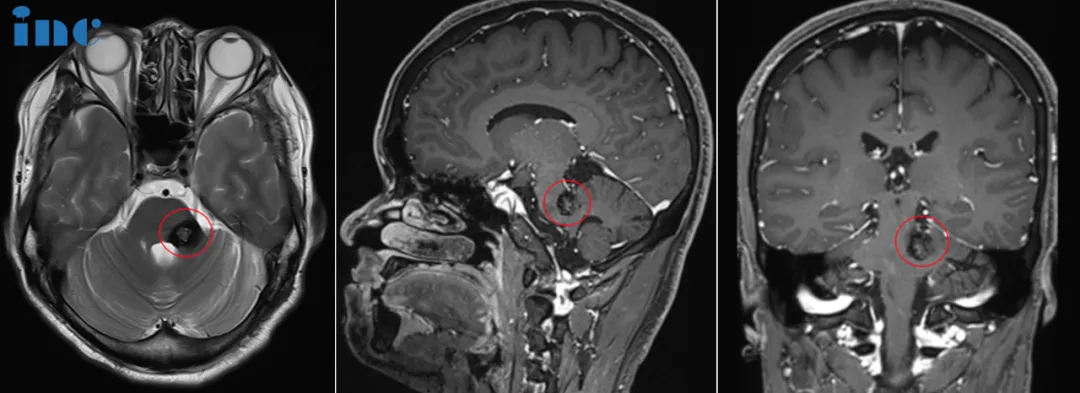

“最新MR顯示,腦干海綿狀血管瘤切得很干凈,沒有明顯副作用。”2024年初,盧先生接到INC巴特朗菲教授的隨訪回復(fù)時(shí),攥著手機(jī)的手終于不再發(fā)抖——這場(chǎng)持續(xù)7年的“顱內(nèi)炸彈”危機(jī),終于迎來(lái)了句號(hào)。

“一開始以為是累著了,拍了CT說(shuō)情況不好,轉(zhuǎn)去上級(jí)醫(yī)院做核磁,才知道是腦干海綿狀血管瘤。”第一次確診時(shí),醫(yī)生建議保守治療,10天后他出院回家,心里還存著養(yǎng)養(yǎng)就好的僥幸。

這份僥幸在2018年被打破。同樣是11月,頭暈再次襲來(lái),核磁顯示“原位出血”。

真正的恐懼發(fā)生在2020年1月23日。頭暈伴著手腳麻木襲來(lái),他被直接送進(jìn)ICU,一住就是5天。這次出血后,右手右腳開始麻痹,走路像踩在棉花上,左耳朵還總傳來(lái)“放鞭炮”似的響聲。“各大醫(yī)院都去了,教授們都說(shuō)手術(shù)風(fēng)險(xiǎn)太大,讓接著保守。”盧先生說(shuō),那時(shí)的他像被困在迷宮里,看著癥狀一天天加重,卻連“出口”在哪都不知道。

“不能再等了。”2023年,盧先生在病友圈聽說(shuō)了巴特朗菲教授——這位專注腦干手術(shù)30多年的專家,有上千臺(tái)成功案例。他立刻通過INC聯(lián)系到巴教授,聲音帶著顫抖:“我2016年確診,已經(jīng)3次出血,能找教授手術(shù)嗎?”

巴教授的視頻會(huì)診給了他希望:“沒有藥物或放療能治,只有手術(shù)全切才能除風(fēng)險(xiǎn)。因?yàn)楝F(xiàn)在是有輕微的神經(jīng)功能癥狀,我做過很多類似的海綿狀血管瘤的手術(shù),也沒有出現(xiàn)更多的這種新發(fā)的神經(jīng)功能障礙,所以我對(duì)于手術(shù)還是很有信心的”

2023年11月6日,手術(shù)如期進(jìn)行,在國(guó)內(nèi)神外團(tuán)隊(duì)的配合下,巴教授順利為盧先生全切腫瘤。

術(shù)后第1天,盧先生就轉(zhuǎn)出ICU,轉(zhuǎn)入普通病房,術(shù)前擔(dān)心的面癱也都沒有發(fā)生。